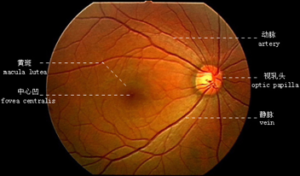

人类眼底的正常形态

人类眼底结构由视盘(也称视乳头)、视网膜和视网膜血管组成。

视盘呈粉红色,边界清晰。

视网膜动脉和静脉由视盘沿着四个象限的方向(即颞上、颞下、鼻上、鼻下)发散,形成许多小分支。正常的视网膜动静脉管径比大约为2:3。

黄斑呈椭圆形,是靠近视网膜中心的色素区域。它的颜色较深,直径约5.5毫米。黄斑中心为中央凹。